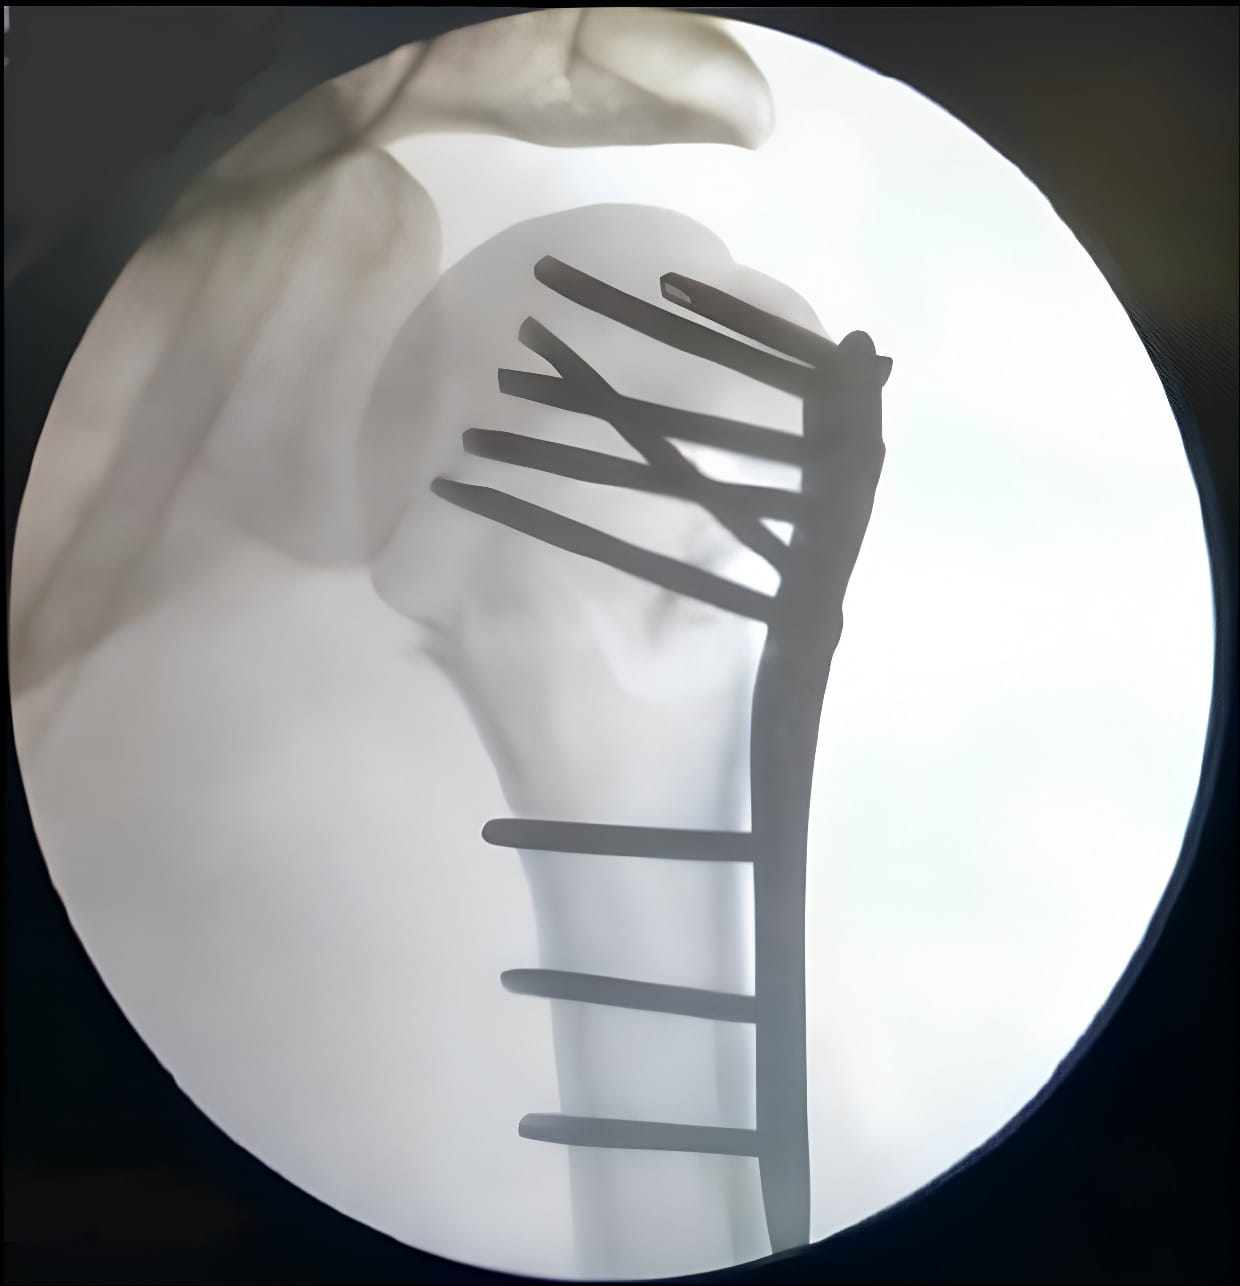

Fracture and Trauma Surgery

Arthroscopic Surgery